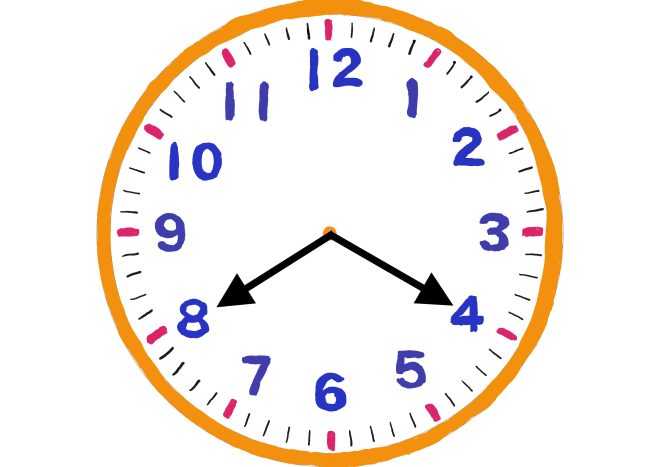

肛門嚢(肛門腺)は、肛門の4時と8時の位置にある器官で、臭気の強い分泌液を排泄し、ワンちゃん同士がお互いを認識したり、縄張りを主張するために使われています。トリミングや病院などで定期的にケアすることも多いため、ワンちゃんの飼い主様には身近なワードではないでしょうか。